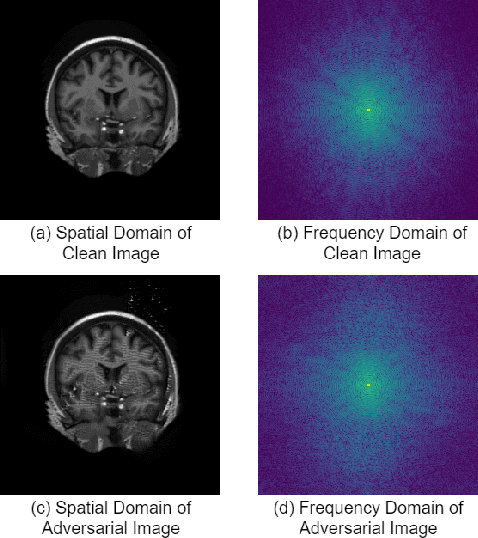

Abstract:This paper presents a novel yet efficient defense framework for segmentation models against adversarial attacks in medical imaging. In contrary to the defense methods against adversarial attacks for classification models which widely are investigated, such defense methods for segmentation models has been less explored. Our proposed method can be used for any deep learning models without revising the target deep learning models, as well as can be independent of adversarial attacks. Our framework consists of a frequency domain converter, a detector, and a reformer. The frequency domain converter helps the detector detects adversarial examples by using a frame domain of an image. The reformer helps target models to predict more precisely. We have experiments to empirically show that our proposed method has a better performance compared to the existing defense method.